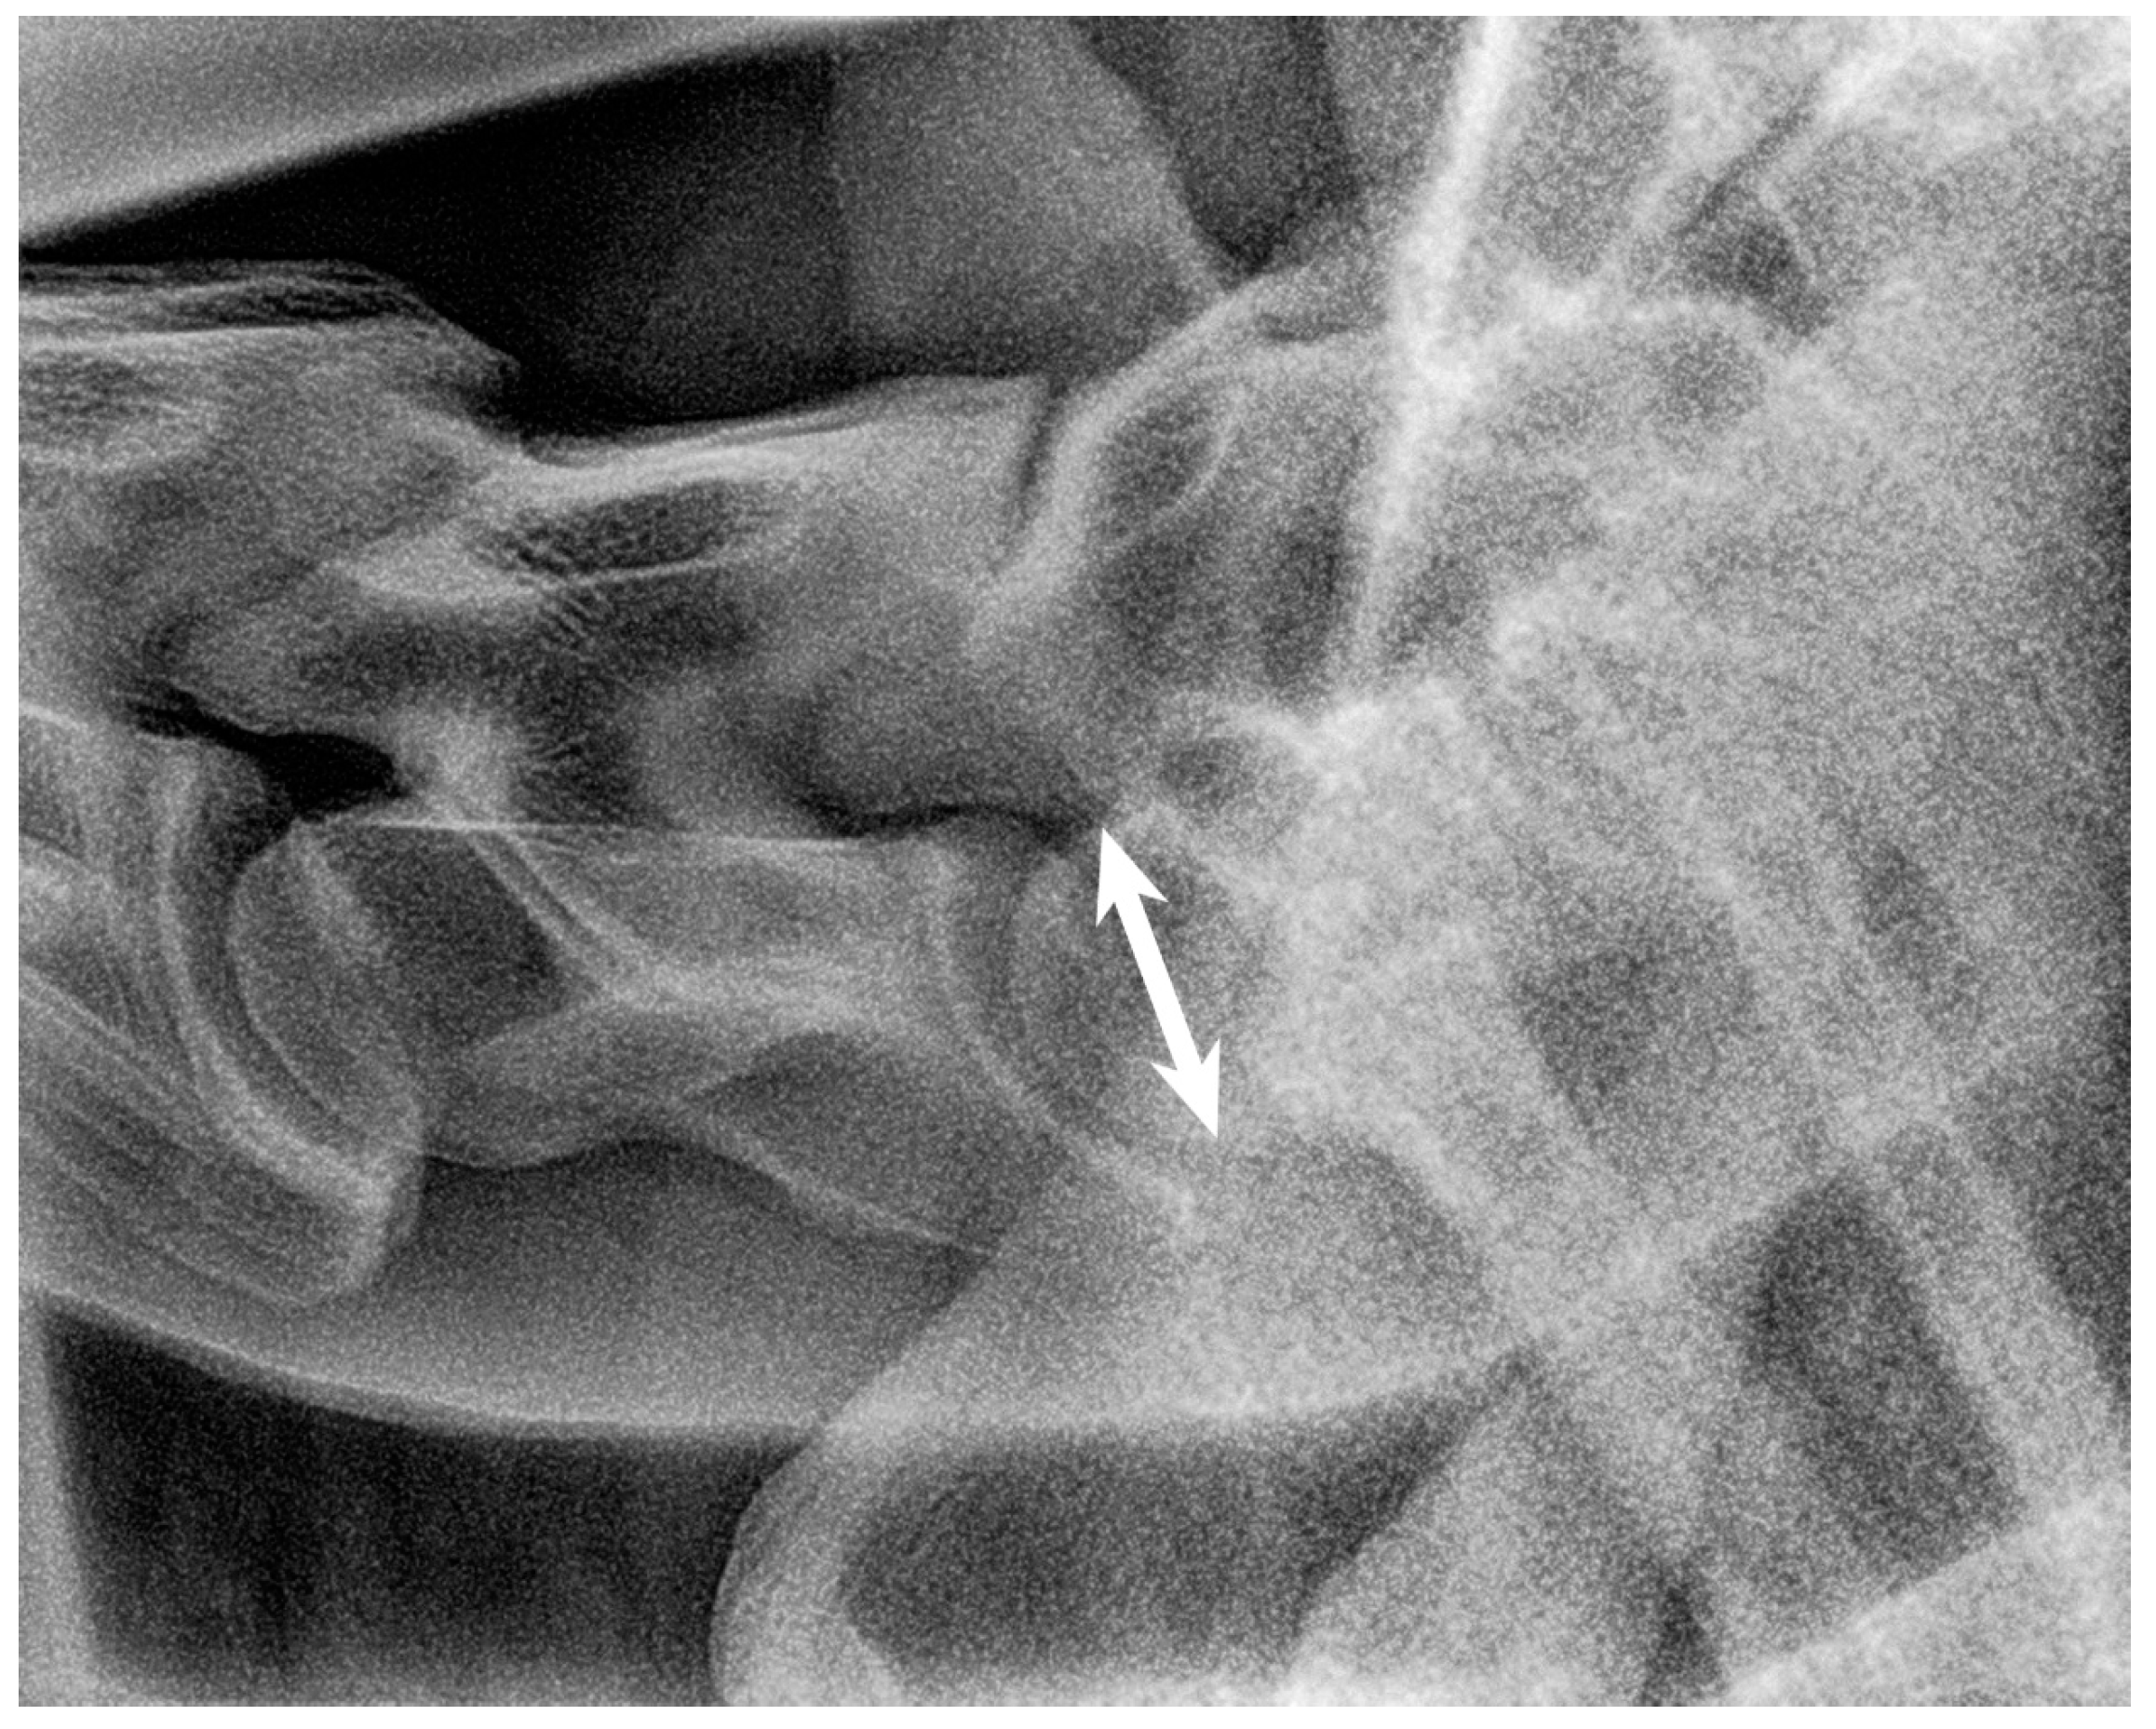

2.3. Radiographic Method

2.4. Classification System